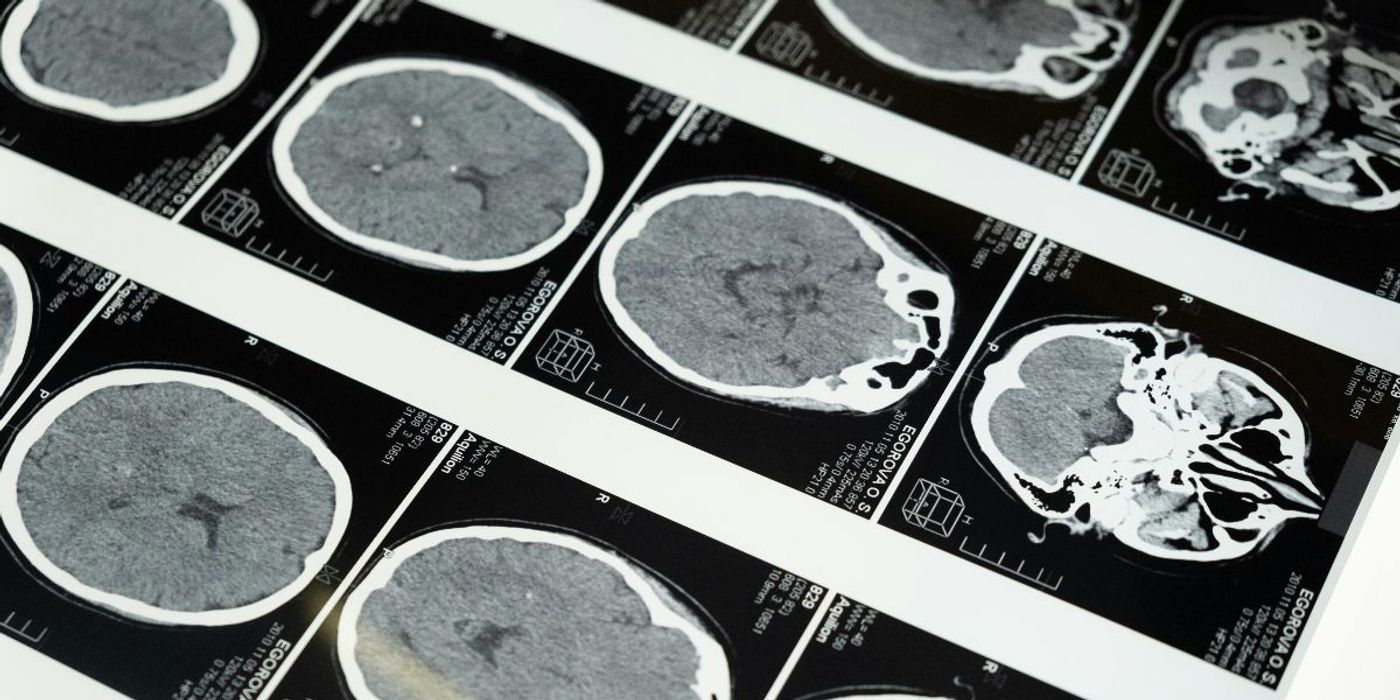

Traumatic brain injury (TBI) in older adults is linked to higher rates of dementia, found a new study published in the Canadian Medical Association Journal